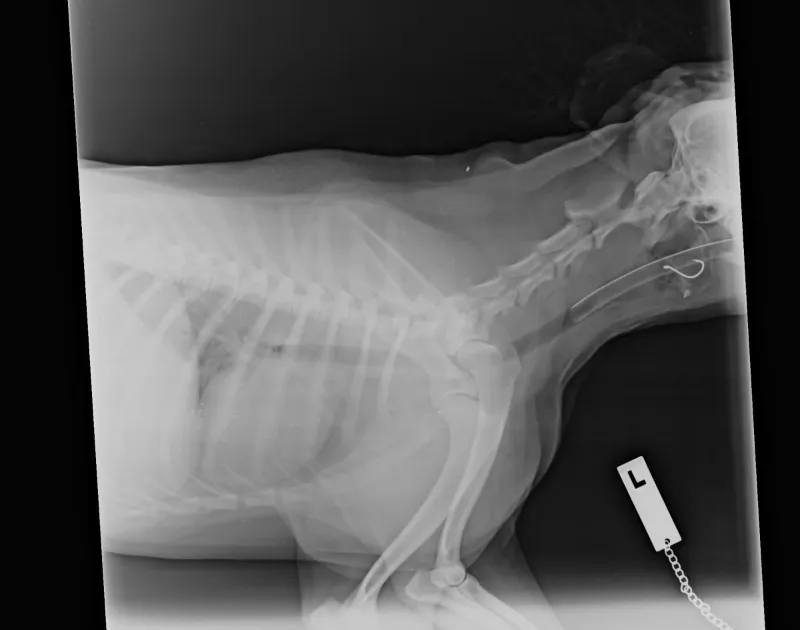

After chewing on a puffer fish at the beach, he became paralysed and needed oxygen to help him breathe. His companion that day, a dog from another family, also became ill and required ventilation. Thankfully, they both recovered fully. In the image, you can see Sam very relaxed, and the tape is where his nasal O2 catheter was removed.

A picture of dog having x-ray

And it’s not just marine life you need to watch out for. We had another unlucky dog, Lulu, who snatched something from the grass near a waterway so fast her owner had no time to stop it. She started gagging and became extremely distressed. It turned out to be a fish hook stuck in her throat. We were able to remove it safely and uneventfully under anaesthetic, but this could have been much worse.